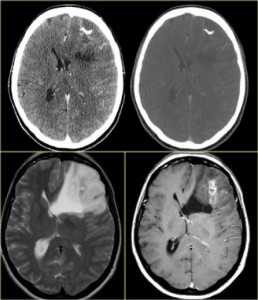

КТ и МРТ головного мозга. Аксиальные КТ, Т2-взвешенные МРТ и МРТ головного мозга с контрастировавшем. Вовлечение коры при олигодендроглиоме.

- Вовлечение коры - олигодендроглиома, ганглиоглиома, дисэмбриопластическая нейроэпителиома